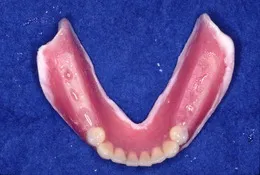

総入れ歯(フルデンチャー)

総入れ歯で肝心なのは顎(顎堤)にぴったりあっていることと咬み合わせがしっかりしていることでしょう。入れ歯で困っている方には原因があります。丁寧に診査し解決策を探りましょう。

当院では治療用の入れ歯を使って顎にぴったりとあった形を導きます。ぴったりあった入れ歯を入れると口元も自然感を取り戻せます。「急がばまわれ」、少し時間をかけて使いやすい入れ歯を手に入れましょう。

また、咬み合わせは癖が出やすいものです。調和のとれた咬み合わせにするには『咬合採得』の技術が必要です。当院では治療ステップを正確に行うため安定した咬み合わせの総入れ歯を装着できます。

(ティッシュコンディショナーを使った治療義歯で形を合わせていきます。金属製のブレードティースを応用することもあります)

(顎の位置を確認するためにフェイスボウトランスファーを行います。)

(出来上がった入れ歯の咬み合わせを再度確認・調整します)

(顎の形にしっかりフィットして咬み合わせが安定した入れ歯ができあがりました)